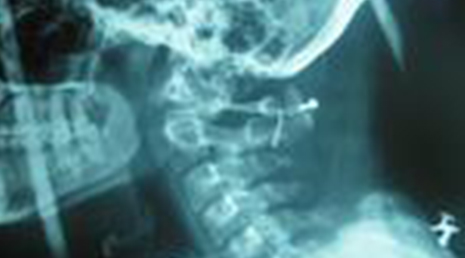

Degenerative Spine

The phrase "degenerative changes" in the spine refers to osteoarthritis of the spine. Osteoarthritis is the most common form of arthritis. Doctors may also refer to it as degenerative arthritis or degenerative joint disease.